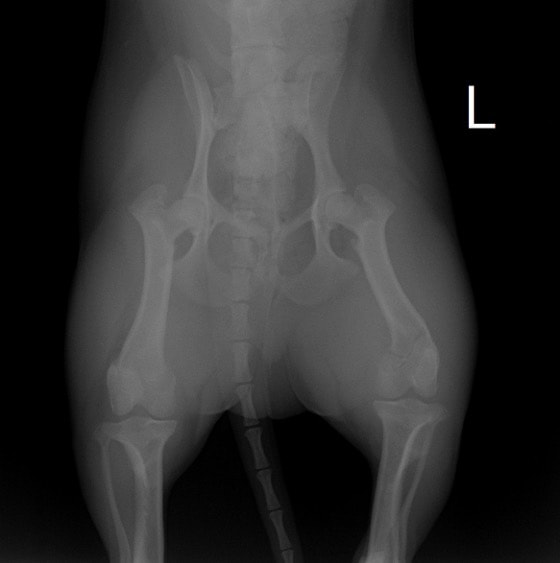

ペルシャ猫 11ヶ月齢 雄

他院にて左大腿骨遠位の成長板骨折(salter-harrisⅠ型)が認められており、治療相談を目的として来院。当院にて、キルシュナーワイヤーを用いたピンニングにより骨折部位の整復を行いました。術後の経過は良好で、現在も経過観察中です。

術前レントゲン

術後レントゲン